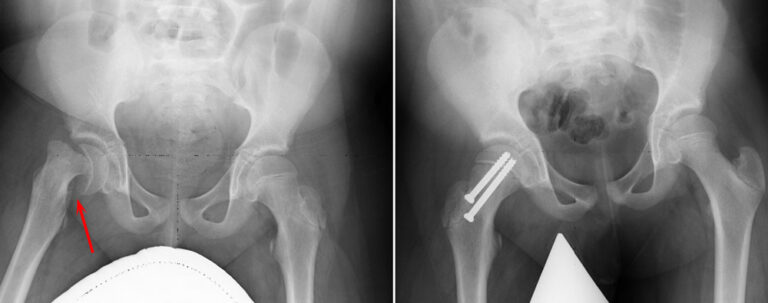

Open Reduction

For patients with unstable SCFE, a more extensive surgical procedure called open reduction may be required. In this approach, the surgeon makes a larger incision in the hip and carefully manipulates the femoral head back into its correct anatomical position.

After repositioning the femoral head, one or two metal screws are inserted to secure the bone and maintain proper alignment until the growth plate naturally fuses. While this procedure effectively restores hip stability, it is more complex and involves a longer recovery period compared to other treatment methods.

(Left) Preoperative X-ray of an unstable SCFE . (Right) Postoperative X-ray shows that the femoral head has been manipulated back into place and screws have been inserted to hold it in place.